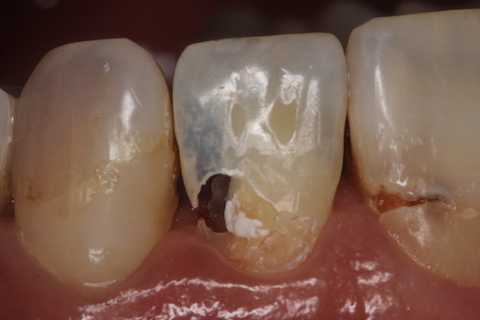

40代女性、右上2、自発痛-

かなりひどい虫歯で、外側表面のエナメル質はなんとか残したが、ペラペラだ。

スプーンエキスカベータで軟化象牙質を剥がすと簡単に露髄した(黄色矢印)。